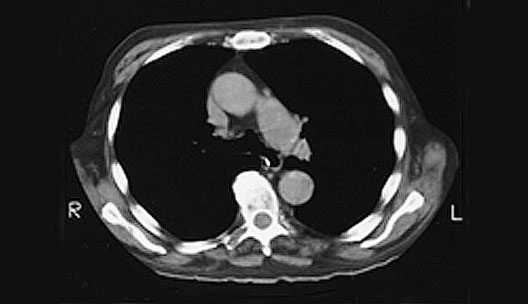

Heart CT

1. Ascending aorta

2. Pulmonary trunk

3. Descending aorta